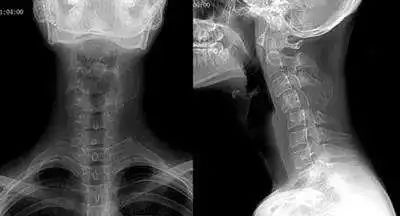

虽然当人体在端坐或站立时,从侧面观察可见颈部似乎是直的,但其实包绕于内的颈椎并不是直的,而是在其中段有一向前凸出的生理弧度,我们把这一向前的弧形凸起称为颈椎的生理弯曲。我们通过X线片检查可见:在各个颈椎椎体后缘都有形成的连续、光滑的弧形曲线,称之为颈椎弯曲。颈椎生理弯曲的存在能增加颈椎的弹性,减轻和缓冲震荡,防止外力对脊髓和大脑的损伤。

长时间不正确的久坐、或是劳累、颈椎缺少活动、脊柱损伤、脊柱钙化等就会导致颈椎生理弯曲变直。颈椎的前凸可逐渐消失,甚至可变直或呈反张弯曲,即向后凸,成为颈椎病在X片上重要的诊断依据之一。